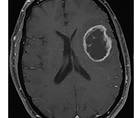

Challenge Case Report: A Woman With a Large Dural-Based Lesion

Javed Khader Eliyas, MD; Rimas V. Lukas, MDJaved Khader Eliyas, MD; Rimas V. Lukas, MD - Imaging & Testing